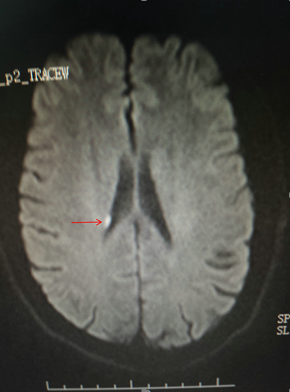

经过全科治疗,患者左侧肢体很快恢复活动,NIHSS评分也变正常,入院第二天肌力就恢复到正常。此时吴伯提出希望可以出院,但我院建议他做再一个MR检查,检查后发现了吴伯的右侧脑室旁急性脑梗死。吴伯今后需终生服药治疗,同时要戒烟、更改生活习惯等。

颅脑MR DWI像显示此次急性脑梗死部位(箭头所指)